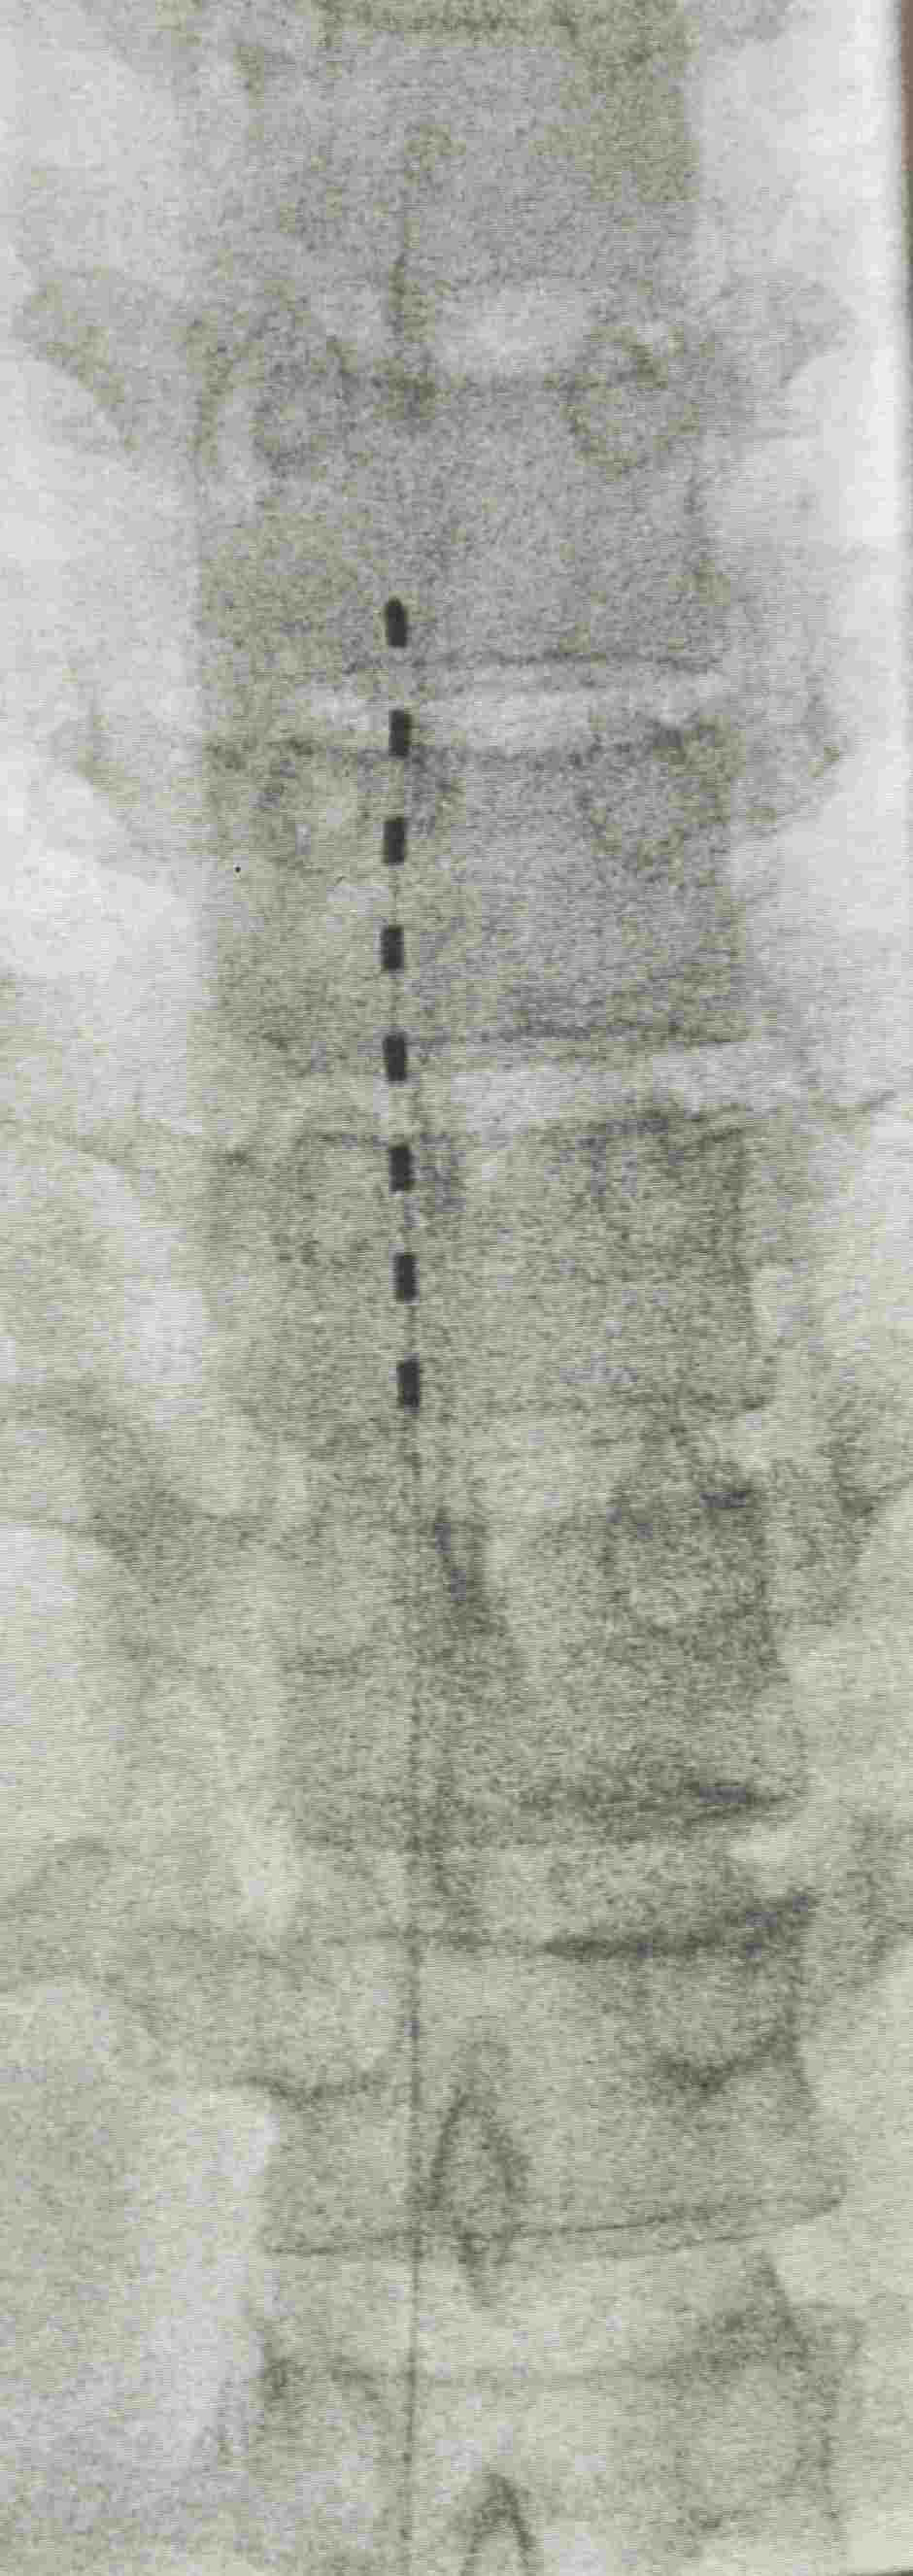

脊髓电刺激: 将电极植入椎管内硬膜外腔,释放微弱电流干扰或阻断疼痛信号上传至大脑。适用于药物和常规介入治疗效果不佳的顽固性PHN。